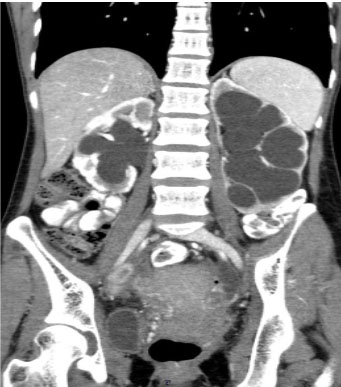

A 28-year-old female presented with massive hematuria with clots. She was seen at the major testing centers and was given massive blood transfusions. Hemoglobin dropped to 4–3.5 g/dL within days of transfusion. She was on treatment for endometriosis and primary infertility. She underwent laparoscopic bilateral oophorectomy and prolonged medical management with danazol, while hematuria continued and became worse. As she presented to us, a papillary lesion was seen projecting through the urethra. Cystoscopic evaluation showed a mass in the supratrigonal area and base. Ultrasound abdomen (USG) and magnetic resonance imaging (MRI) scan showed lesions involving the urinary bladder, uterus and pelvis (Figure 1). Contrast-enhanced computed tomography (CECT) abdomen showed involvement of both ureters in the lower one third, producing massive hydroureteronephrosis (HUN) (Figure 2). However, her creatinine remained stable, and percutaneous nephrostomy (PCN) was deferred. As the exsanguinating hematuria continued despite all therapeutic measures, we noticed a previous report in which a similar case was managed [1] and opted to follow the steps described there, in consultation with the radiation oncology team. With their support, we gave radiotherapy (RT) to the pelvis, as endometrial tissue is very highly radiosensitive. A radiation dose of 20 Gy in 10 fractions with 15 MV photons was delivered to the target. It was delivered as 200 cGy per fraction and 5 fractions a week, in 4 fields (AP, PA, left lateral, and right lateral), and the dose was prescribed to 100% isodense line, treating using 3D CRT technique (Figure 3). The targeted volume for RT was uterine myoma and normal endometrium, along with the lesion infiltrating into the bladder. The response of cessation of bleeding was swift. The HUN also resolved in two weeks. This occurred in the year 2017. The patient was monitored for three years, and now she is completely asymptomatic, except for irregular menstrual periods. The CT scan taken recently showed a normal bladder and upper tracts, and the pelvic endometriosis had disappeared completely (Figure 4).

Figure 4: Significant reduction in the endometrial tissue postradiotherapy.